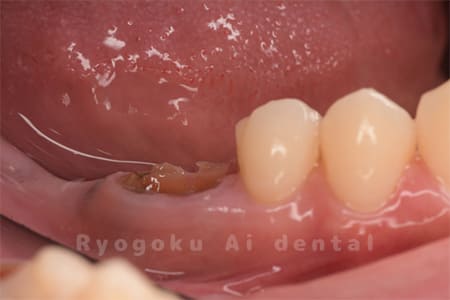

Case14

-

- 抜歯原因

- 重度カリエス

- 治療内容

- クラウンレングスニング治療

- 治療費用

- 44,000円

他院で抜歯と言われた、とのことでご来院された患者さまです。クラウンレングスニングを行い、保存致しました。大変満足して頂けました。